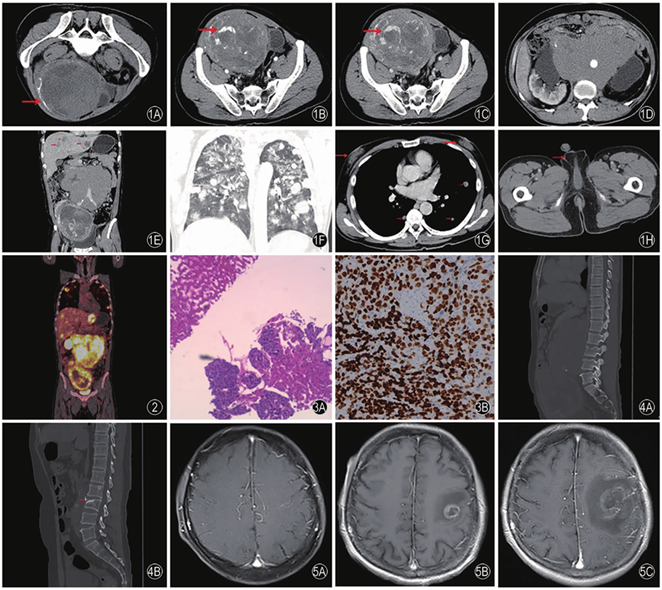

图5 患者的颅脑MRI图像。5A颅脑MRI正常,无转移灶(化疗前);5B颅脑MRI示左侧额叶转移灶,增强呈不均匀环状强化(2020年5月5日);5C颅脑MRI示左侧额叶转移灶较前增大(2020年5月14日)